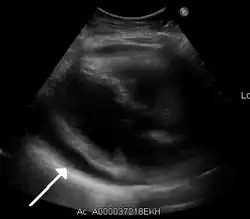

Echocardiogram (ultrasound): when pericardial effusion is suspected, echocardiography usually confirms the diagnosis and allows assessment of the size, location and signs of hemodynamic instability.[4] A transthoracic echocardiogram (TTE) is usually sufficient to evaluate pericardial effusion and it may also help distinguish pericardial effusion from pleural effusion and MI. Most pericardial effusions appear as an anechoic area (black or without an echo) between the visceral and the parietal membrane.[1] Complex or malignant effusions are more heterogeneous in appearance, meaning they may have variations in echo on ultrasound.[5] TTE can also differentiate pericardial effusion based on the size. Although it's difficult to define size classifications because they vary with institutions, most commonly they are as follows: small <10, moderate 10–20, large >20.[5] An echocardiogram is urgently needed for evaluation when there is concern for hemodynamic compromise, a rapidly developing effusion or history of recent cardiac surgery/procedures.[1]

A large anechoic (black) pericardial effusion as seen on ultrasound. Closed arrow: the heart, open arrow: the effusion -